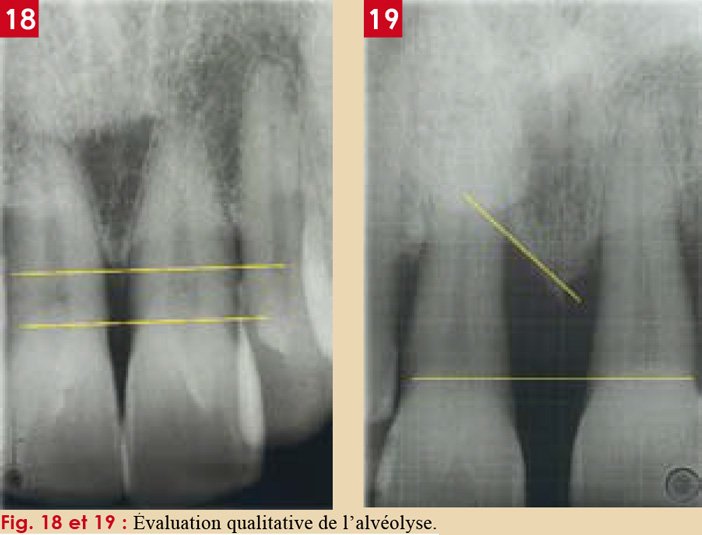

3.2. Forme et dimensions : l’espace en sablier

Sur une coupe longitudinale, l’espace periodontal présente un rétrécissement au niveau du tiers médian de la racine, lui conférant une forme caractéristique en sablier.

Ce rétrécissement correspond à l’hypomochlion — le centre de rotation de la dent lors des mouvements orthodontiques. C’est une notion fondamentale en biomécanique orthodontique.

Selon PRICHAUD, une image d’épaisseur régulière est un signe de normalité. À l’inverse :

- Un élargissement de l’espace desmodontal évoque une surcharge occlusale, un traumatisme ou une parodontite apicale

- L’absence de l’espace desmodontal signe l’ankylose dento-alvéolaire